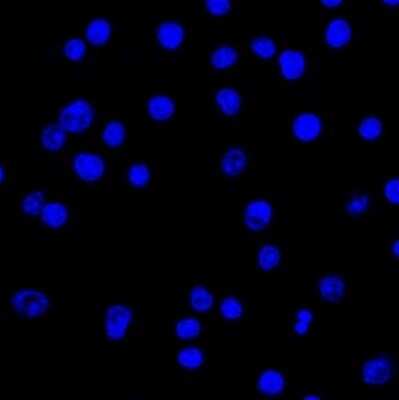

Immunocytochemistry/Immunofluorescence: Lambda Light Chain Antibody (LcN-2) [NBP2-62751] - Confocal Immunofluorescent analysis of Ramos cells using AF488-labeled Isotype Control Monoclonal Antibody (IgG2a) (Green). DAPI was used to stain the cell nuclei (blue). (Negative Control)